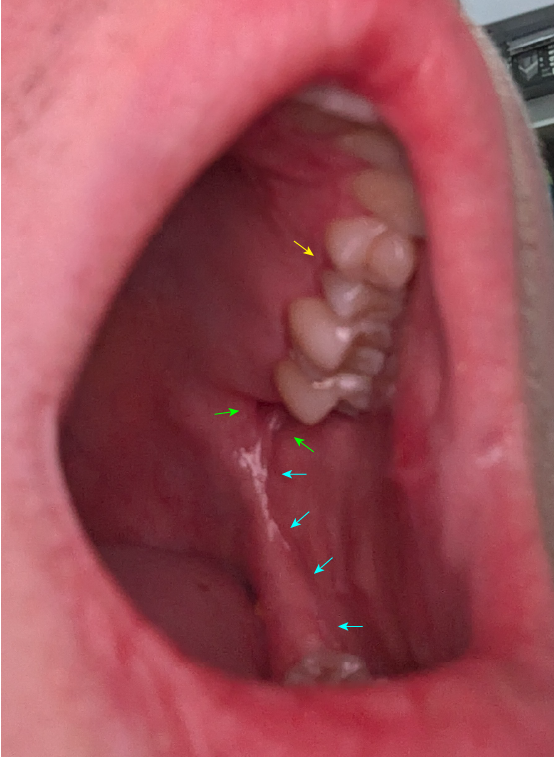

YELLOW: Oral Fistula - A piece of this tooth broke off a few months ago and now fluid leaks from a hole there as well.

GREEN: Oral Fistula.